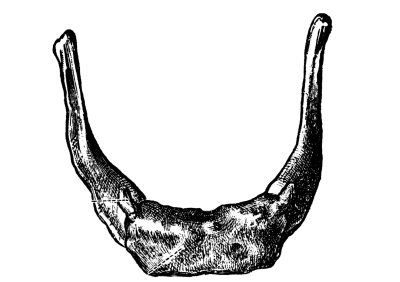

The Cranial Bones, 48—Frontal Bone, 49—Parietal Bones, 49—Occipital Bone, 50—Occipito-frontalis Muscle, 51—Temporal Bones, 51—Sphenoid or Wedge Bone, 52—Ethmoid Bone, 53—Turbinated Bones, 53—Ossification of Sutures, 53—Bones of the Face, 53—Superior Maxillary Bones, 54—Antrum of Highmore, 54—Malar or Cheek Bones, 54—Lachrymal Bones, 54—Palate Bones, 54—Nasal Bones, 55—Vomer, 55—Inferior Turbinated Bones, 55—Inferior Maxillary Bone or Lower Jaw, 55—Sublingual Gland, 56—Submaxillary Gland, 56. |

| The Organs of Special Sense | 57 |

The Nose, 57—The Sense of Smell, 58—The Mouth, 59—The Hyoid Bone, 60—The Teeth, 60—The Sense of Taste, 61—Salivary Glands, 61—The Tonsils, 62—The Ear, 63—Eustachian Tubes, 63—Sensation of Hearing, 65—The Eye, 66—Lachrymal Gland, 68—Coats of the Eye, 68—Light Rays and Sight, 70—Accommodation, 72—Color Perception, 73. |